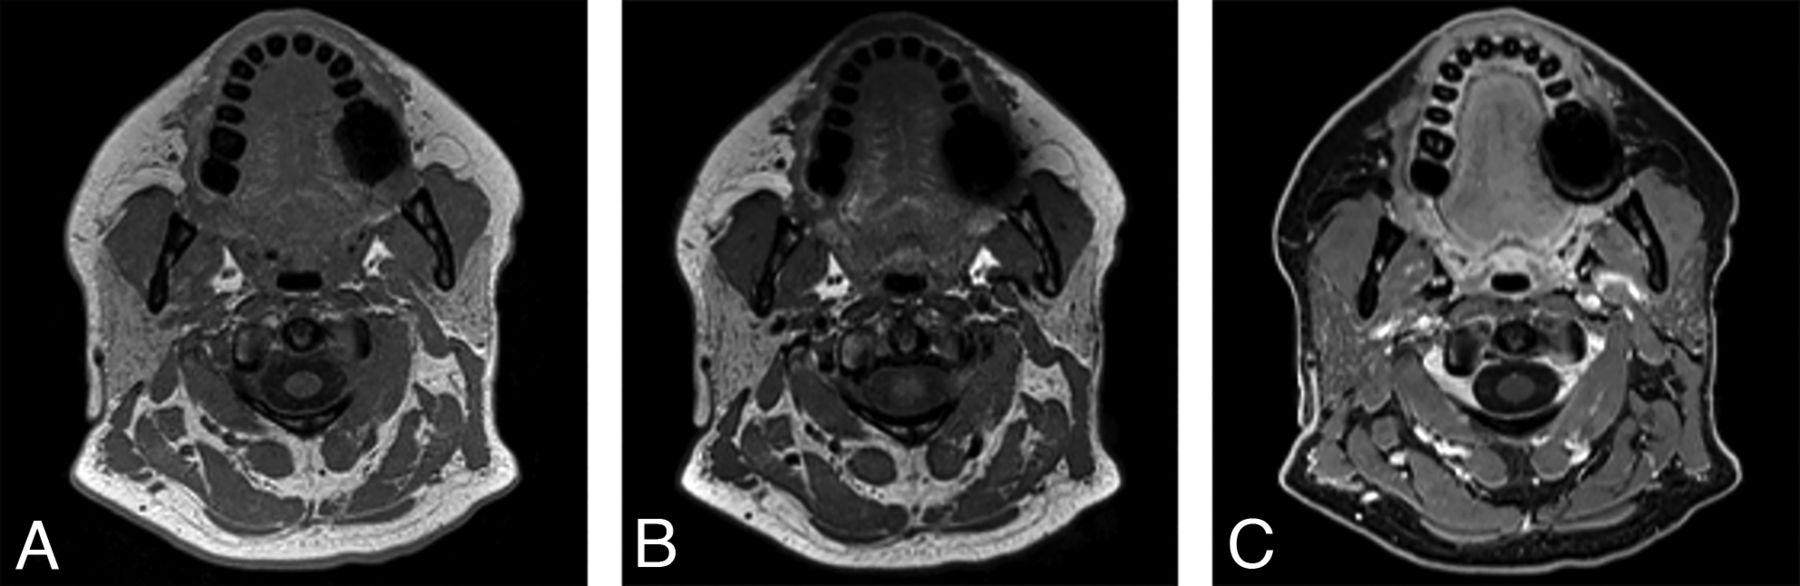

For the nonfocal whole-neck protocol, we acquired data in the sagittal plane, which minimizes the scan range and eliminates the potential for wrap artifacts from the body and vertex scalp. Given that this protocol is used for identification of gross soft-tissue abnormalities without the necessity for finer spatial detail, we acquired it at 1-mm isotropic resolution. However, even with 1-mm3 voxels, this sequence can often more clearly show smaller lesions than in what we traditionally called high-resolution 2D acquisition images, which were submillimeter in-plane but with 3-mm or thicker section thickness. An example is provided in Fig 2 of images from a 92-year-old woman with a small focal preauricular metastasis of cutaneous squamous cell carcinoma invading the parotid gland.

A 92-year-old woman with squamous cell carcinoma. A, T1 SPACE sequence performed in the full-neck MR imaging protocol with 2.7-mm3 (1.4 mm isotropic) voxels during early optimization iterations reformatted into the axial plane clearly shows a cutaneous preauricular lesion (arrow) that is not visible due to volume averaging on the 2D T1-weighted image (B) with 1-mm3 (4 × 0.5× 0.5 mm) voxels. The T1 VIBE Dixon (C) reformatted image in the axial plane shows the associated infiltrating tumor into the parotid gland (arrow) to advantage compared with the 2D T1-weighted image (D) with spectral fat suppression. The case convinced us that the SPACE sequence was a reasonable alternative to the 2D standard-of-care and led us to improve the spatial resolution of the SPACE sequence. These images were obtained contemporaneously on a 3T Magnetom Vida system.